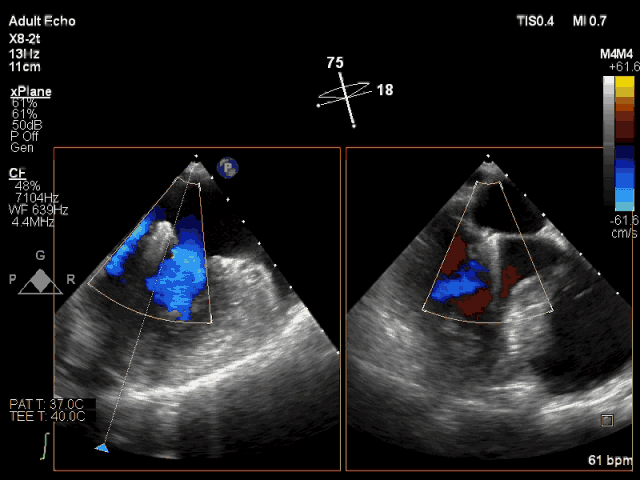

夹合即刻CDFI示轻微MR

此次转播心脏超声机器为最新一代Philips EPIQ 7C,使用X8-2t食道探头进行术中经食道超声,采用TrueVue实时三维双容积视野同时显示二尖瓣左房观和左室观。新一代超声机器分辨率高、图像处理速度快、图像界面舒适,使得手术非常顺利,手术转播的导管操作时间仅用8分钟。患者术后即刻效果满意,反流从重度减少到轻度。